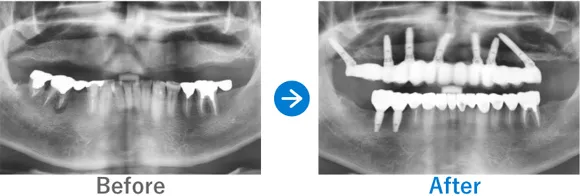

上下義歯の状態からインプラント治療後に自信を取り戻された方

上下義歯(入れ歯)ほとんど歯が残っていない、残存歯は上顎1本下顎5本のみ。

上顎骨がやせていて普通にはインプラントが出来ない状態。

上顎ザイゴマインプラントでALLON4、下顎ALLON4

10,703,000円(上顎7,128,000円、下顎3,575,000円/内訳:上顎オールオン4(ノーベルザイゴマインプラント4本)、下顎オールオン4(ストローマンインプラント4本)、3Dモデルガイド*、仮歯、セデーション、ボツリヌストキシン注射、3D模型、保証10年)

来院の背景

60代前半から現在の義歯を使っている。初めはピッタリだったが、だんだんと義歯がゆるくなり、鈎歯(こうし)が折れた。歯がダメになったら、インプラントを検討しようと思っていた。ご主人のご友人がインプラントをしたため興味を持ったが、金額もかかるため、家族には相談せずに来院された。

治療結果

上顎ザイゴマインプラント4本。下顎ALLON4で行った。治療完了後、現在もメンテナンスで来院中で経過良好。口元が綺麗になり、お化粧をするなど美意識が高まり、おしゃれに気をつかうようになったとのこと。「笑顔が増えて、よく外出するようになりました。自信がつきました。」